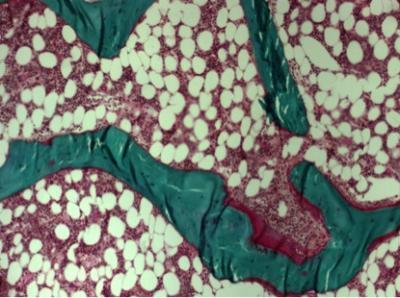

Bone samples were investigated using bone histomorphometry, a microscopic method that provides information about bone metabolism and remodelling. In children with vertebral fractures, there were changes in bone composition, such as lower carbonate-to-phosphate-ratio and increased collagen maturity, which could explain the increased fracture risk. The results also suggest that in children who have undergone kidney, liver or heart transplantation, the various changes related to bone microarchitecture and turnover may be more important predictors of fracture risk than lowered bone mineral density alone. Early detection of such changes in bone quality could help prevent fractures.

This image shows a bone biopsy.

(Photo Credit: UEF, KUH)